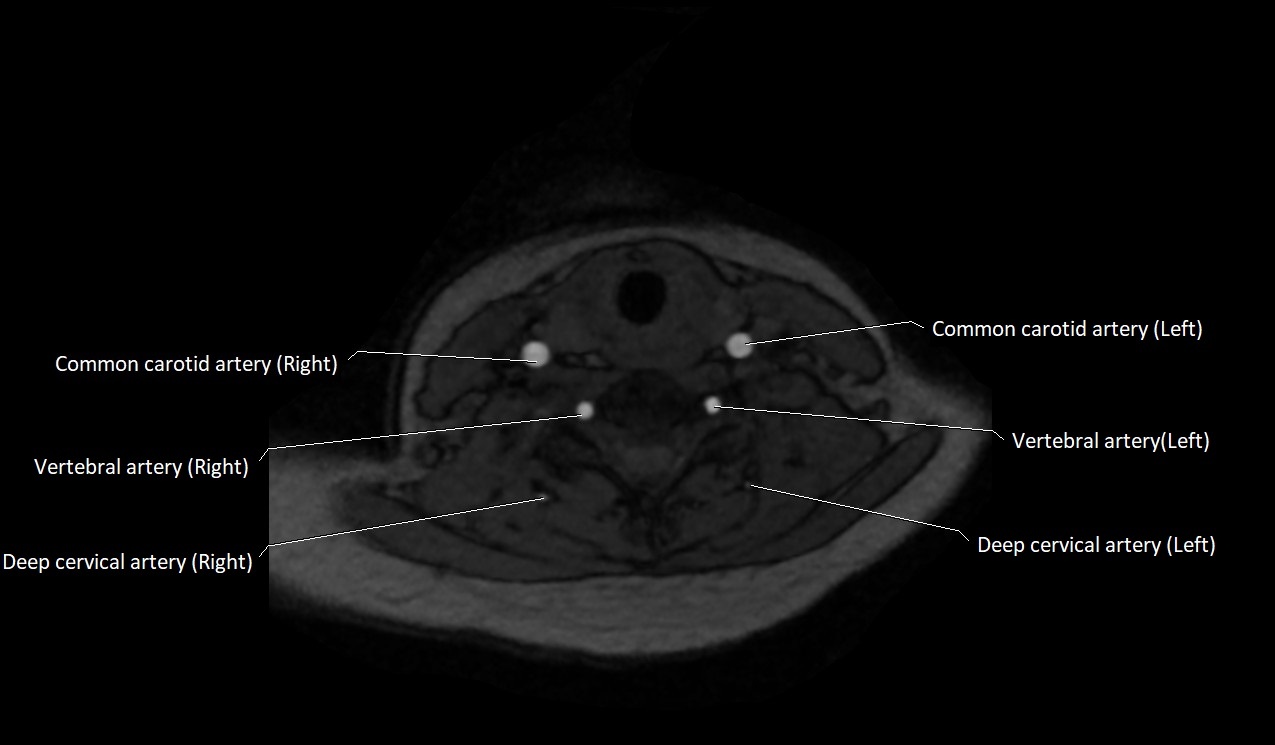

MRI images

image